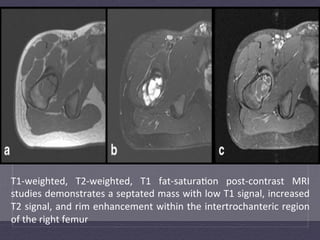

T1-­‐weighted,   T2-­‐weighted,   T1   fat-­‐satura:on   post-­‐contrast   MRI   studies  demonstrates  a  septated  mass  with  low  T1  signal,  increased   T2  signal,  and  rim  enhancement  within  the  intertrochanteric  region   of  the  right  femur